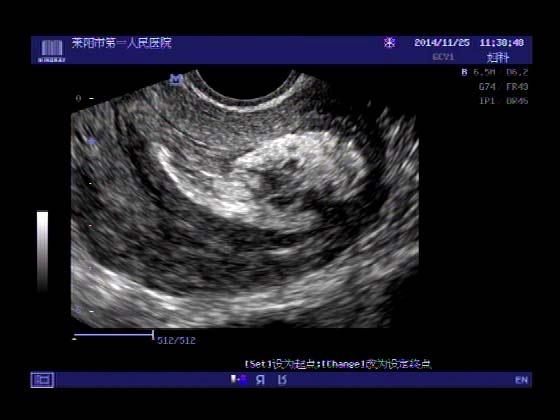

超声入门贴379---------粘膜下肌瘤(阴超的魅力)

女,43岁,月经量多3个多月,加重一个月

外院彩超检查提示:子宫后肌壁略高回声团------肌瘤?息肉?,盆腔少量积液

今天来我院检查:

巧妇难为无米之炊,经腹部超声确实很难定,阴超一目了然,乡镇医院诊断水平的提高更迫切的需要高档仪器的引进!